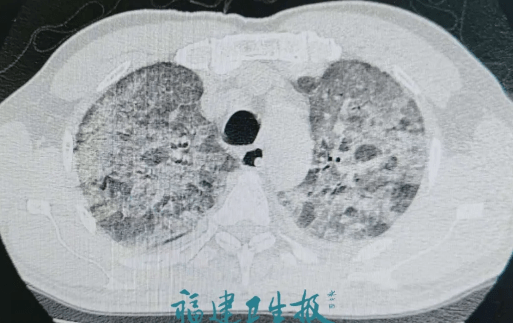

50岁左右的陈先生(化名) , 在福州于山上当保安 , 前段时间 , 他莫名吃不下饭、呼吸加重、咳嗽咳痰发热 , 持续一周 。 从两肺完整正常到全白 , 仅一天!病情进展速度不亚于重症新冠肺炎!

没想到 , 在胸外科住院一天就出现发热、呼吸困难加重、咳嗽咳痰 。 CT复查显示 , 双肺出现了明显的炎症进展;仅24小时之内 , 从完全正常到两肺全白!